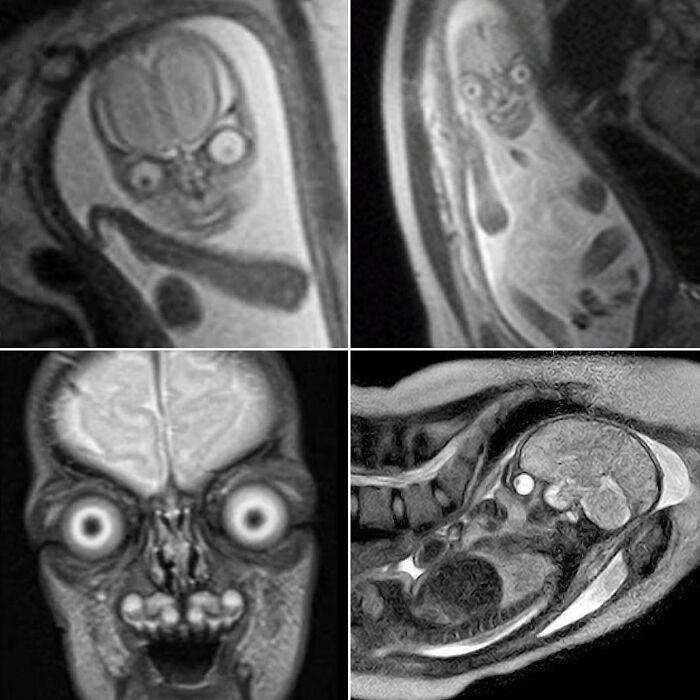

#3 Genuine MRI Scans Of Human Babies In The Womb

Possessing menacing eyes and devilish grins, you would be forgiven for assuming these were just aliens from a Hollywood sci-fi blockbuster.

These images were circulating on social media apps and while some suggest they have been traumatised by viewing such discomforting images, others seem to find them comical.

Some users even believed the fetus was an extra-terrestrial being.

Yet, believe it or not, they are not fake.

Instead, they are genuine MRI scans of human babies in the womb.

MRI scans are different to ultrasounds. Parents are not regularly offered MRI throughout their pregnancy and will typically only have the scan if there is a concern for the child’s growth and development.

For example, they can help define and detect neck, thoracic, abdominal and spinal malformations in fetuses.

When used during pregnancy, however, MRIs can produce a very life-like image of their baby.

The detailed black and white images burst the bubble of many parents who blindly believe their tiny tot is going to be adorable through and through.

One user said MRIs are discouraged during pregnancy because ‘people would realise they’re incubating nightmare demons and would be rightfully terrified’.

We can confirm these images are authentic and real.

MRI uses magnetic fields and radio waves to produce detailed images of the inside of the body.

The eyes and brain have high levels of ‘signal’ — a radio wave — which causes them to appear brighter and stand out on the scan.

Other parts of the body give off lower levels, and therefore appear darker.